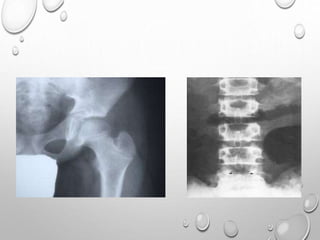

PELVIS – MULTIPLE DENSE CURVED LINES PARALLELING THE ILIAC

CREST

Chest radiograph in an infant demonstrates

overall increased density of osseous

structures due to accumulation of immature

Generalized increased density of bones &

alternating areas of increased & decreased

density in metaphyses (bone-within-bone

appearance).